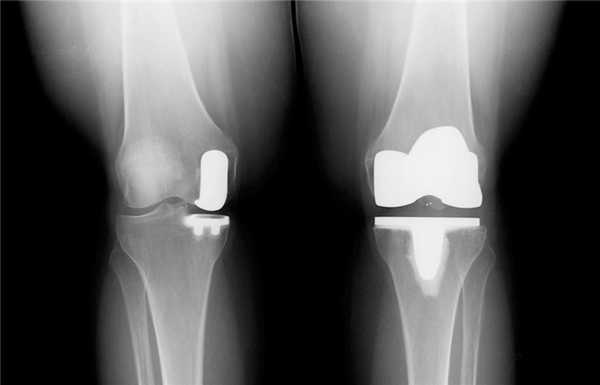

Вы уже знаете, что бывает полное и частичное эндопротезирование коленного сустава, где в первом случае лечение подразумевает полноценную замену суставных поверхностей, а во втором - имплантацию поврежденного участка одного из мыщелков. Соответственно, протезы классифицируются на тотальные, одномыщелковые и ревизионные для замены импланта.

- После постановки однополюсной системы максимально сохраняется собственный костно-хрящевой сегмент и не затрагиваются связки, кстати, они должны быть в хорошем состоянии.

Одномыщелковая замена сустава на рентгене.

Сравнение двух типов операций.

Одномыщелковое протезирование подразумевает срок службы небиологического устройства максимум 7 лет. Тотальное замещение предусматривает время службы вживленного механизма от 15 лет. Ревизионное переносится сложнее, а риск инфекции и других негативных явлений почти в 2 раза выше, чем после первичной операции.